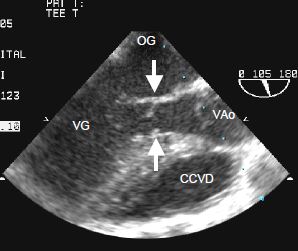

- CIV de la chambre d'admission (5-10% des cas): elle fait partie du canal AV et apparaît en dessous et entre les feuillets septaux de la valve mitrale et de la valve tricuspide (Vidéo et Figure 15.30); elle peut être spontanément occluse par le feuillet septal de la tricuspide.

Vidéo: CIV de la chambre d'admission située sous la valve tricuspide; elle est typique du canal atrio-ventriculaire.

Figure 15.30 : Images ETO de CIV de la chambre d’admission, situées sous la valve tricuspide, dans la partie proximale du septum interventriculaire. Ce type de CIV fait partie du canal AV, en l’occurrence partiel puisqu’il n’y pas de CIA ostium primum associée. Les insertions septales de la valve mitrale et de la tricuspide sont au même niveau, ce qui est typique du canal AV.